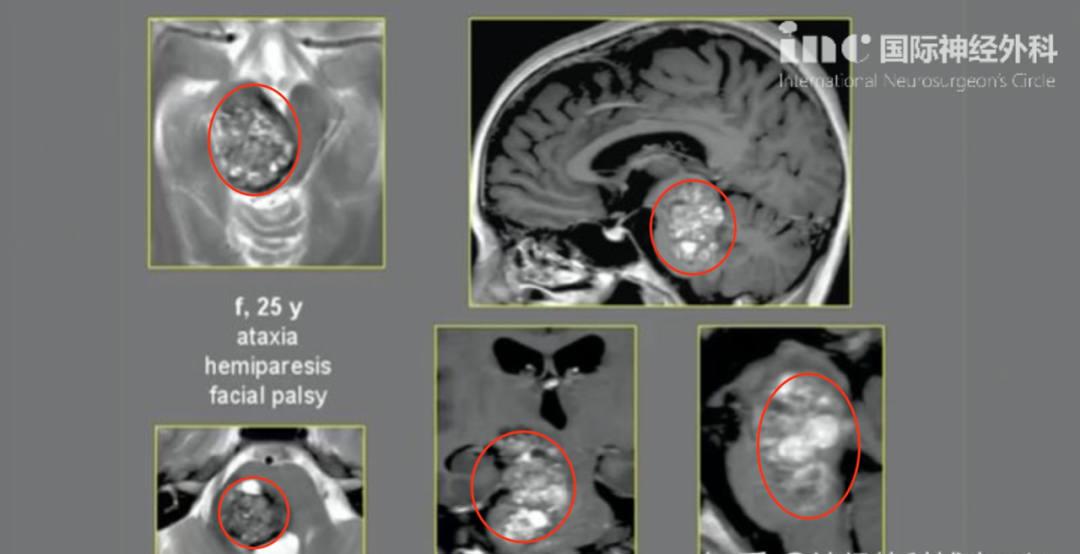

腫瘤伴鈣化、瘤內(nèi)出血,并伴有腦積水。磁共振成像(MRI)顯示一個可能起源于透明隔的異質(zhì)性強(qiáng)化腫瘤,填充在側(cè)腦室和第三腦室的大部分區(qū)域。

第一次左額半球間經(jīng)胼胝體切除術(shù)后,CT掃描顯示腦室內(nèi)和腔內(nèi)出血。第二次經(jīng)右頂葉經(jīng)皮質(zhì)入路成功實現(xiàn)次全切,術(shù)后顯示為WHO 2級室管膜瘤。隨后,為進(jìn)一步控制殘余腫瘤,魯特卡教授為患兒制定了局部放療方案。

幾年后,隨訪時發(fā)現(xiàn)腫瘤再次生長,因此在部分切除后再次進(jìn)行放療。此后6年,室管膜瘤無復(fù)發(fā),病情穩(wěn)定。